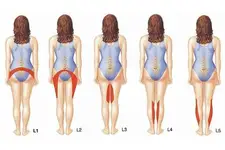

Bel fıtığı, omurlar arasındaki disklerin dış tabakasının yırtılması ve iç kısmının dışarı çıkması sonucu oluşan bir durumu tanımlar. Bu rahatsızlık, sıklıkla şiddetli ağrı, uyuşma, zayıflık ve hareket kısıtlılığı gibi semptomlara yol açar. Bel fıtığına sahip bireylerin fiziksel aktivite yapma yetenekleri sınırlı olabilir, ancak uygun spor ve egzersiz programları, bu kişilerin sağlığını iyileştirebilir. Bu makalede, bel fıtığı olan bireyler için spor yapmanın faydaları detaylandırılacaktır. 1. Ağrı Yönetimi Bel fıtığı, genellikle ağrıya neden olur. Ancak düzenli spor ve egzersiz yapmak, ağrıyı hafifletebilir. Egzersiz, vücudun doğal ağrı kesici mekanizmalarını tetikler ve endorfin salgılar. Ayrıca, kasları güçlendirerek bel bölgesindeki yükü azaltır.

5. Spor Türleri ve Öneriler Bel fıtığı olan bireyler için önerilen spor türleri, düşük etkili egzersizlerdir. Bu tür egzersizler, omurgaya fazla yük bindirmeden güçlenmeye yardımcı olabilir.